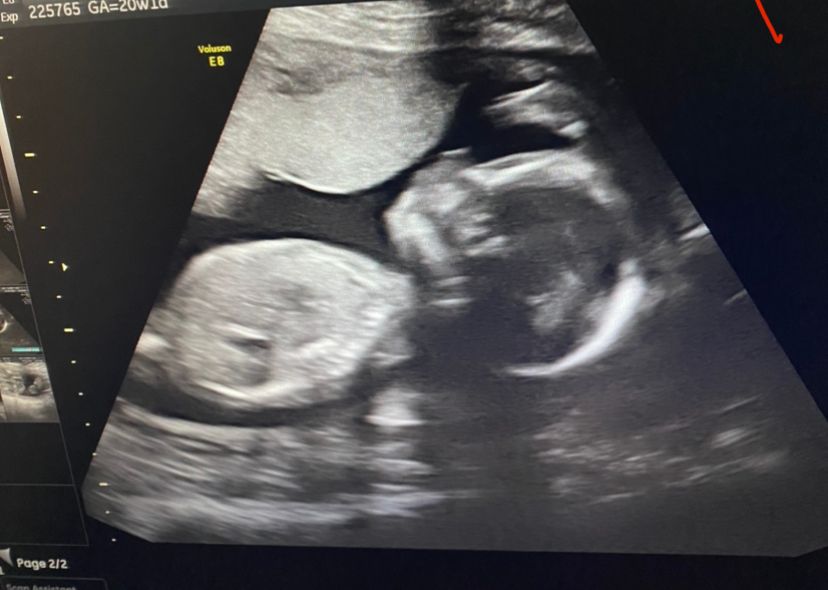

Результаты 2 скрининга: всё хорошо, вес 350 грамм, показатели в норме

418гр была на втором скрининге 😁

У меня через неделю только скрининг, будет 21 неделя) Думаю будем около 400г уже

Хороший вес) 400 весели на втором скрининге )